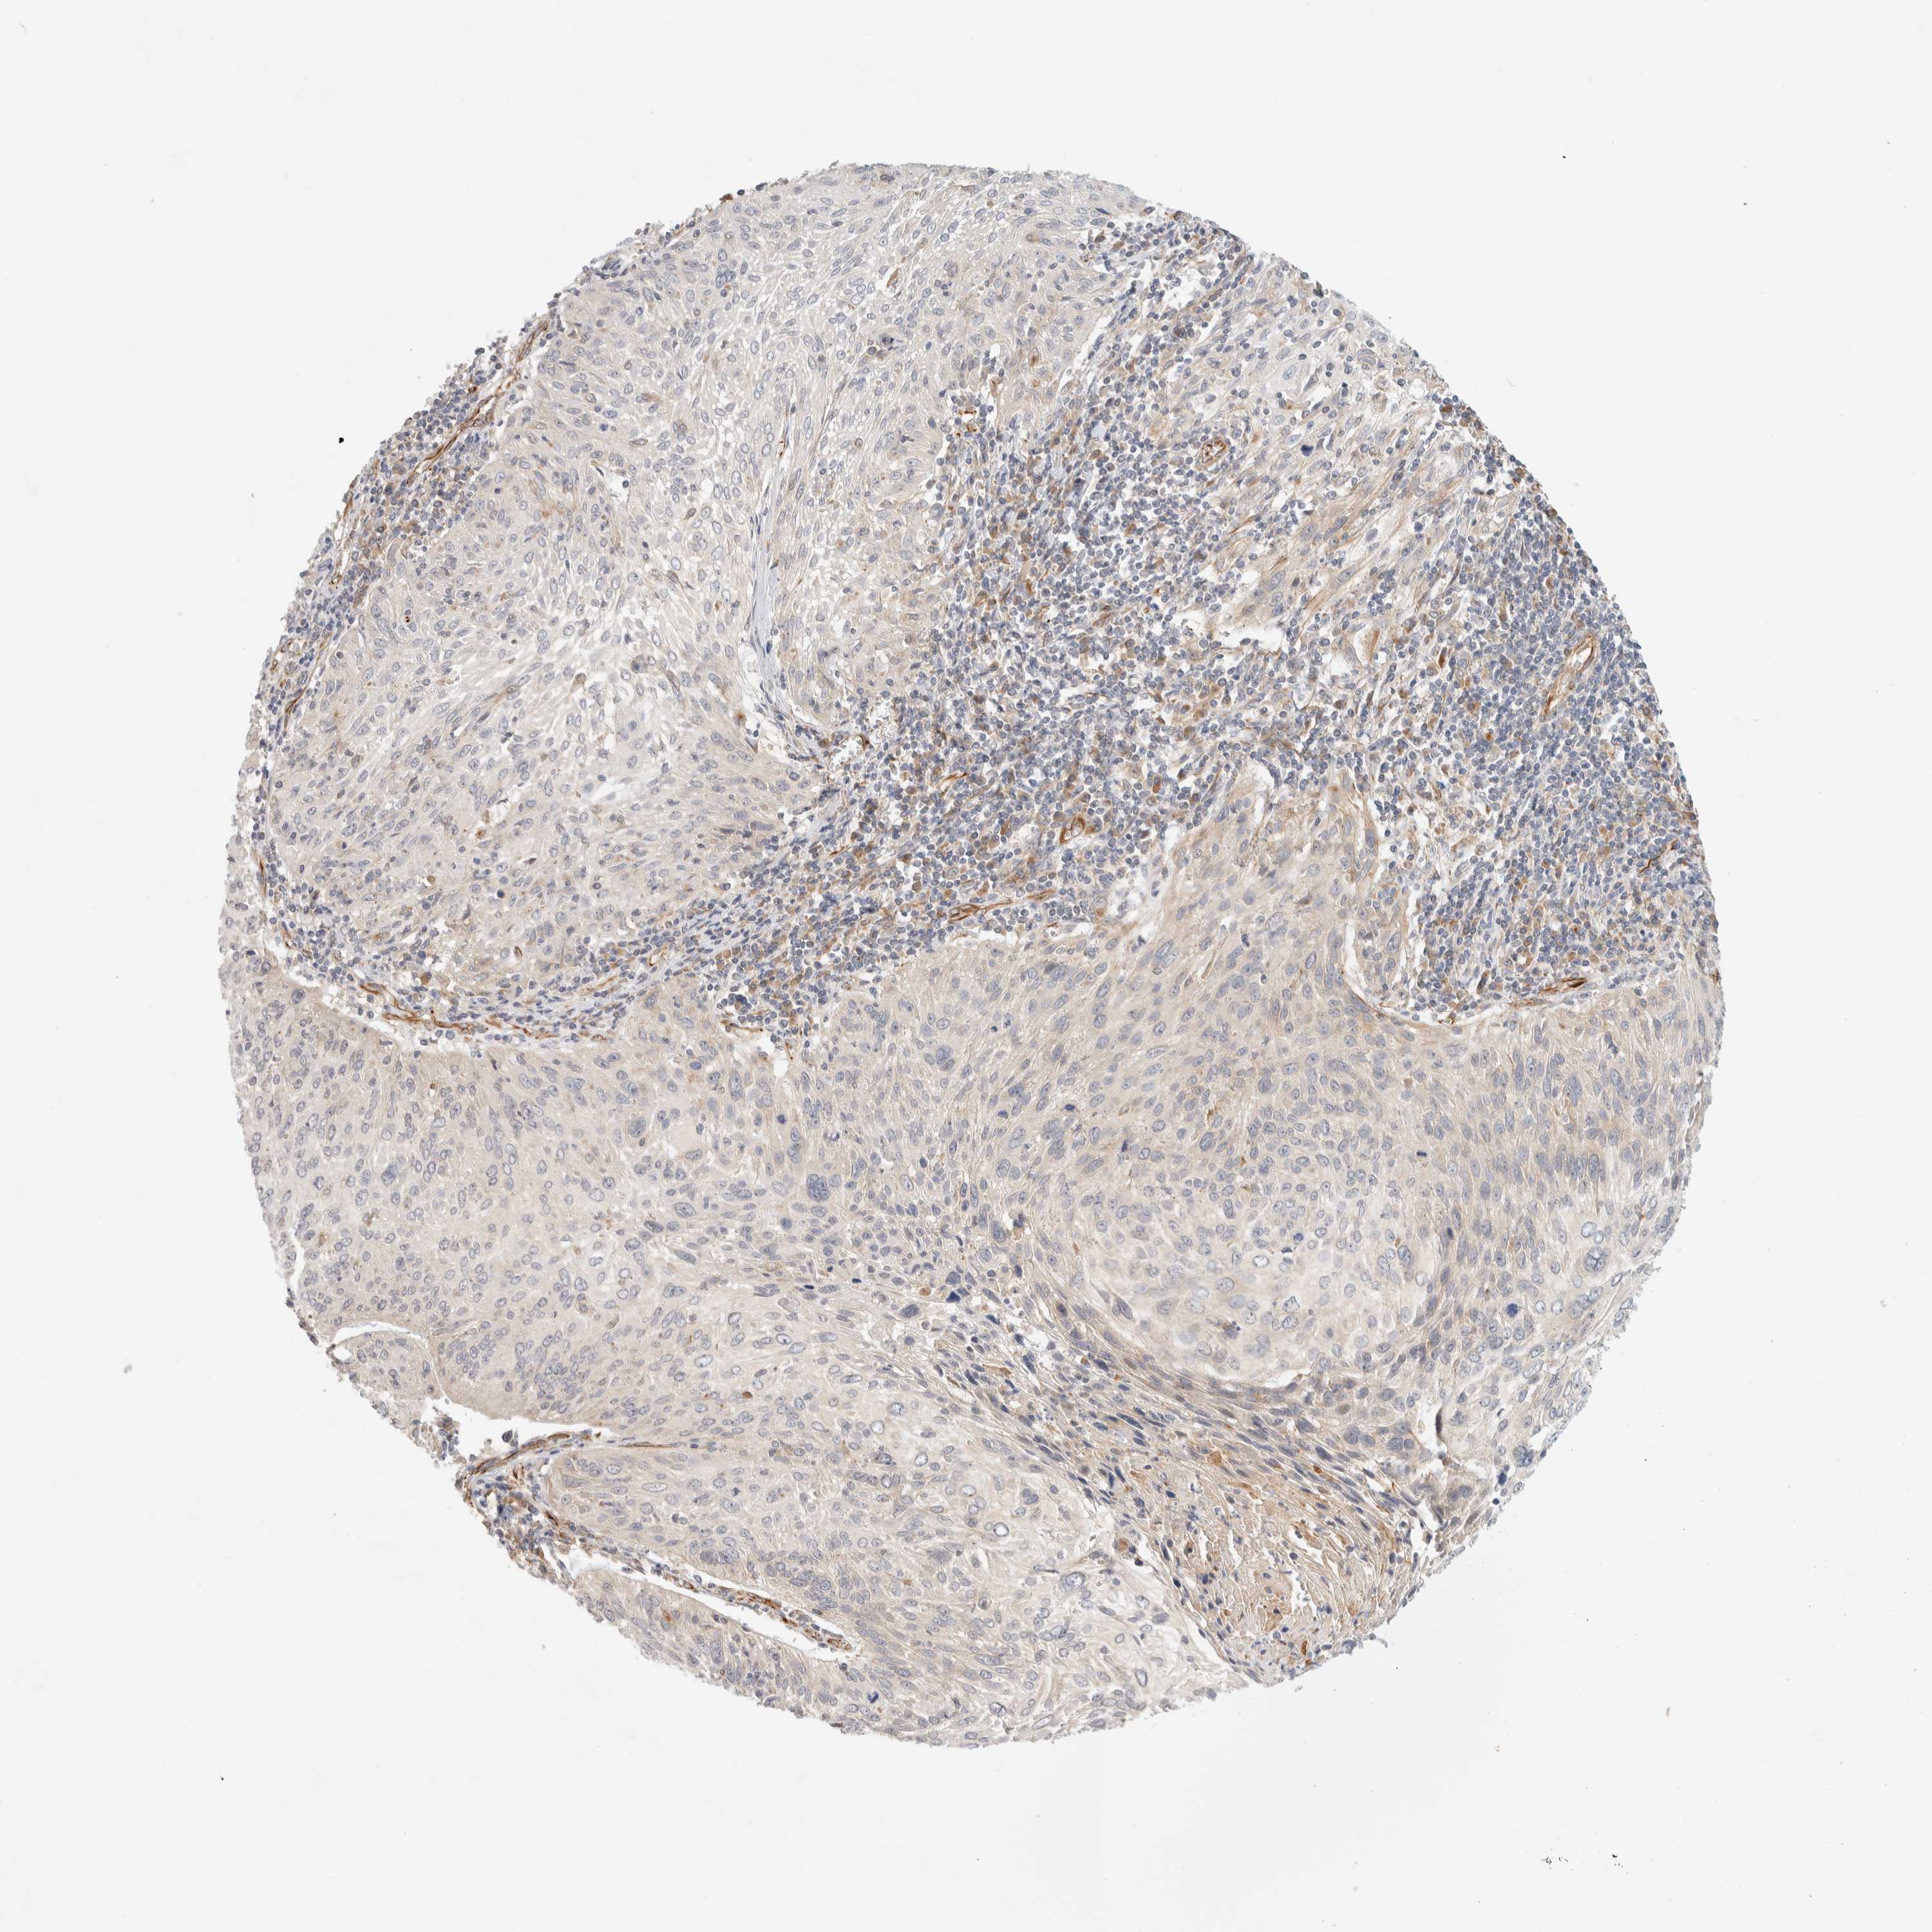

CERVICAL CANCER - Protein expressioni

A mouse-over function shows sample information and annotation data. Click on an image to view it in a full screen mode. Samples can be filtered based on level of antibody staining by selecting one or several of the following categories: high, medium, low and not detected. The assay and annotation is described here.

Note that samples used for immunohistochemistry by the Human Protein Atlas do not correspond to samples in the TCGA dataset.

Antibody stainingi

Antibody staining in the annotated cell types in the current human tissue is reported as not detected, low, medium, or high, based on conventional immunohistochemistry profiling in selected tissues. This score is based on the combination of the staining intensity and fraction of stained cells.

Each image is clickable and will lead to virtual microscopy that enables deeper exploration of all samples and also displays staining intensity scores, fraction scores and subcellular localization as well as patient and tissue information for each sample.

Antibody HPA001869

Antibody HPA023882

Staining

High

Medium

Low

Not detected

Intensity

Strong

Moderate

Weak

Negative

Quantity

>75%

75%-25%

<25%

None

Location

Nuclear

Cytoplasmic/membranous

Cytoplasmic/membranous,nuclear

Squamous cell carcinoma, NOS

Adenocarcinoma, NOS